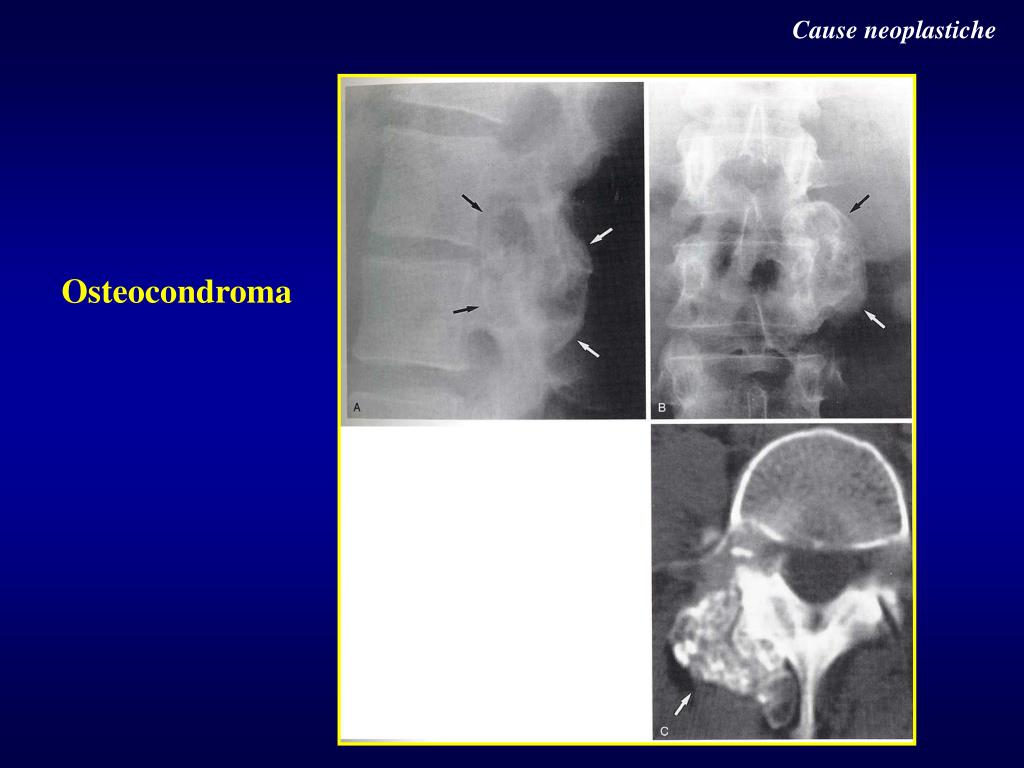

12. 4-Cause neoplastiche • Tumori primitivi • Metastasi ossee • Mieloma multiplo, linfoma

14. Cause neoplastiche Osteocondroma